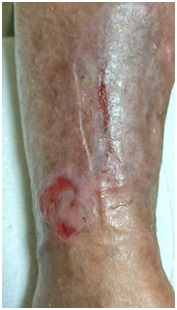

A los 22 días del inicio de la terapia de compresión hubo que utilizar venda de crepé al no estar limpias y secas las vendas de baja elasticidad (y no disponer de más en el centro). En la siguiente cura se apreció una ampolla en la zona perimaleolar externa de unos 3 x 3 cm, que se desbridó y se curó con alginato (Figura 4). El resto de los vendajes se siguieron realizando siempre con baja elasticidad.

Figura 4: Evolución a los 22 días. Aparición de ampolla por roce de venda de crepé.